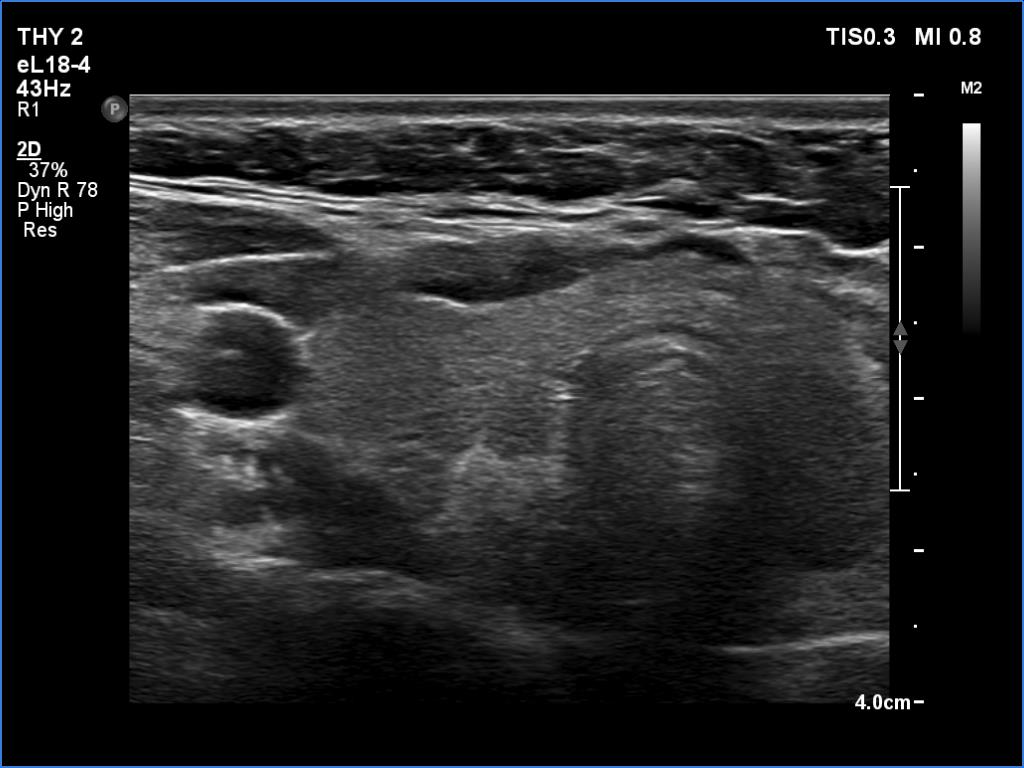

Ultrasonography. The thyroid was echonormal. There was a moderately hypoechoic lesion in the lower pole of the right lobe. The lesion presented no suspicious findings.